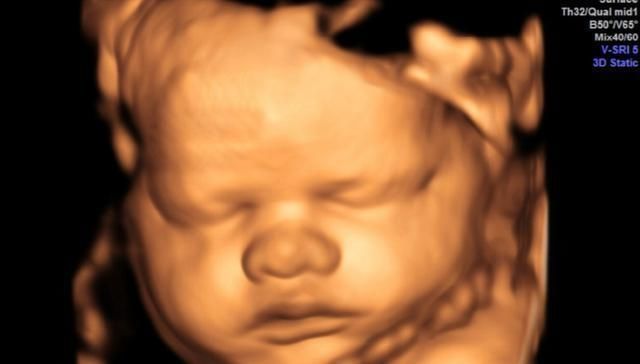

怀孕期间最重要的一项检查是大排畸检查,可以做三维彩超也可以做四维彩超。排畸检查都是绕不过去的检查,因为太重要了。

排畸检查可以查到胎儿的头面部、大脑、内脏器官、四肢、脊柱等外观是否正常,如果孩子有异常问题,需要孕妈妈们早做准备,别等到生下来再发现,到时候会给家庭带来精神和经济负担。